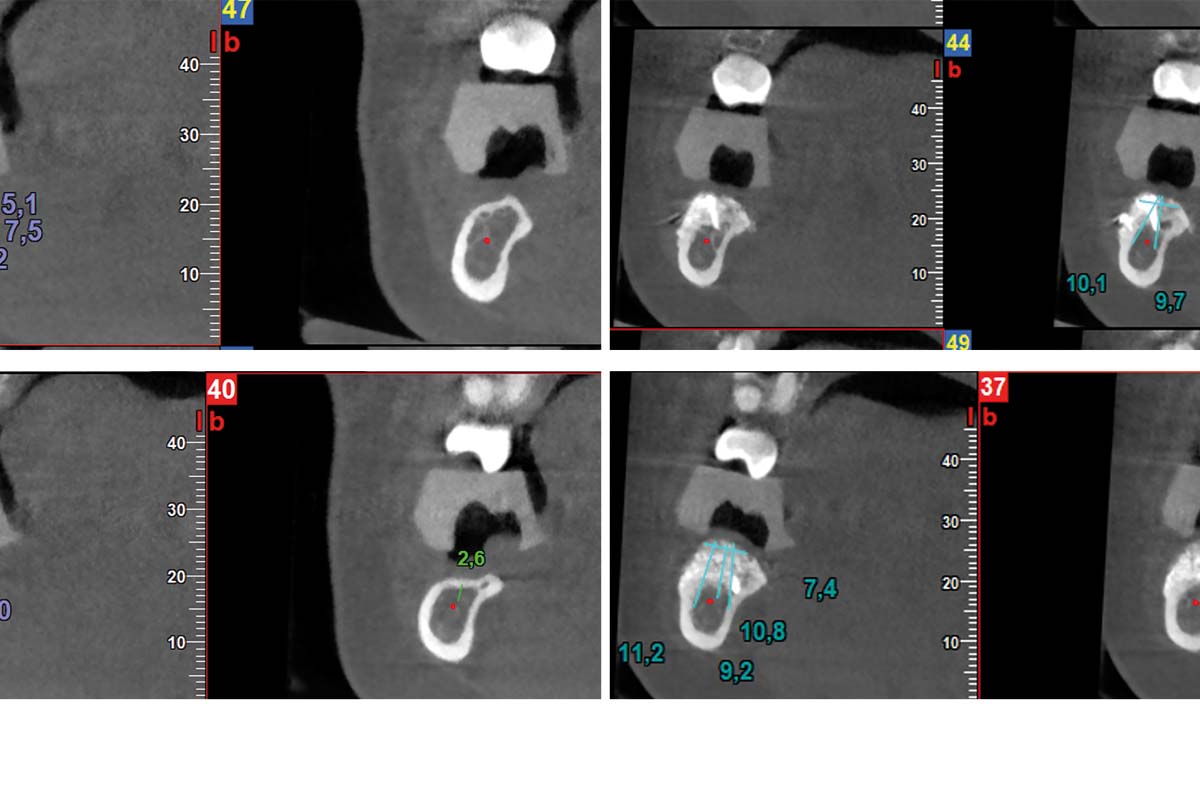

08/10 - Pre- and post-operative CBCTs.

Vertical and horizontal GBR using permamem®, cerabone® and autologous bone - Dr. D. B. Hangyasi